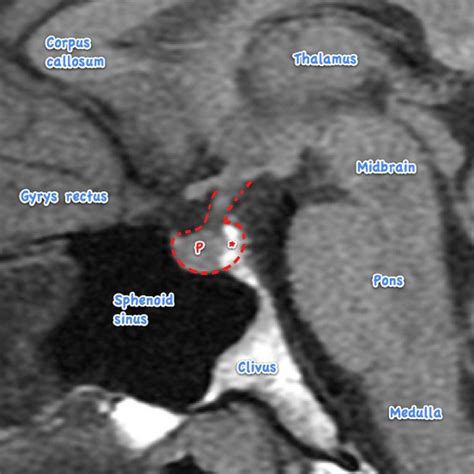

When patients present with symptoms related to hormonal dysregulation, a healthcare provider may order imaging to investigate the pituitary gland. This gland sits within a bony structure called the sella turcica. Because this area is quite intimate, standard brain scans may not always offer the resolution required to see micro-adenomas—very small tumors that can significantly affect hormone production. A dedicated pituitary gland MRI focuses specifically on this region, ensuring that even minute structural changes are identified.

Once the images are acquired, they are sent to a radiologist—a doctor who specializes in medical imaging. The radiologist carefully reviews the scans for any signs of enlargement, masses, or structural abnormalities within the pituitary gland or the surrounding tissues, such as the optic chiasm. The findings are documented in a comprehensive report, which is then sent to the physician who ordered the scan. Your doctor will then correlate these findings with your blood work and clinical symptoms to determine the next steps in your care.